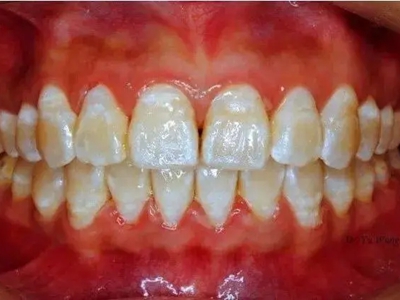

牙釉质发育不全牙齿上出现白色的斑块图

牙釉质发育不全患者牙釉质表面出现白垩色釉质,表现为牙齿表面色泽不均匀,一般无自觉症状,并且此时牙冠形态较为完整,顶端出现小的缺损。